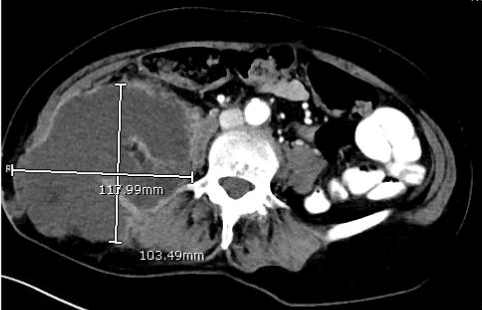

CT abdomen/pelvis revealed a large right psoas abscess measuring 12x10x12 cm (Figure 1) which extended through the right abdominal wall into subcutaneous tissue. Ultrasound-guided aspiration suggested that this was likely an abscess, as the aspirate was negative for malignancy and tuberculosis. The patient underwent incision and drainage of this in theatre with drainage of approximately 1200 ml of fluid. This cultured Citrobacter koseri and Bacteroides fragilis. She had a percutaneous drain left in situ and received intravenous antibiotics (initially ceftriaxone and metronidazole, then broadened to meropenem, then to piperacillin and tazobactam) for two weeks in total, until repeat imaging showed a reduction in the size of the collection to 2x6x3 cm. The drain tube was then removed, and she was discharged with a two-week course of oral amoxicillin/clavulanic acid. An outpatient colonoscopy performed five months post discharge was unremarkable.

Figure 1. CT at initial presentation, demonstrating a large right retroperitoneal abscess extending beyond the right psoas muscles into the subcutaneous tissues of the right loin area.